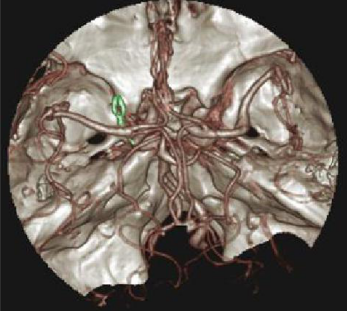

在整體的影像鏈環節進行了改進确保高清晰的圖像。實現了圖像的各向同性,任意方向的 MPR 圖像具有相同的圖像質量。